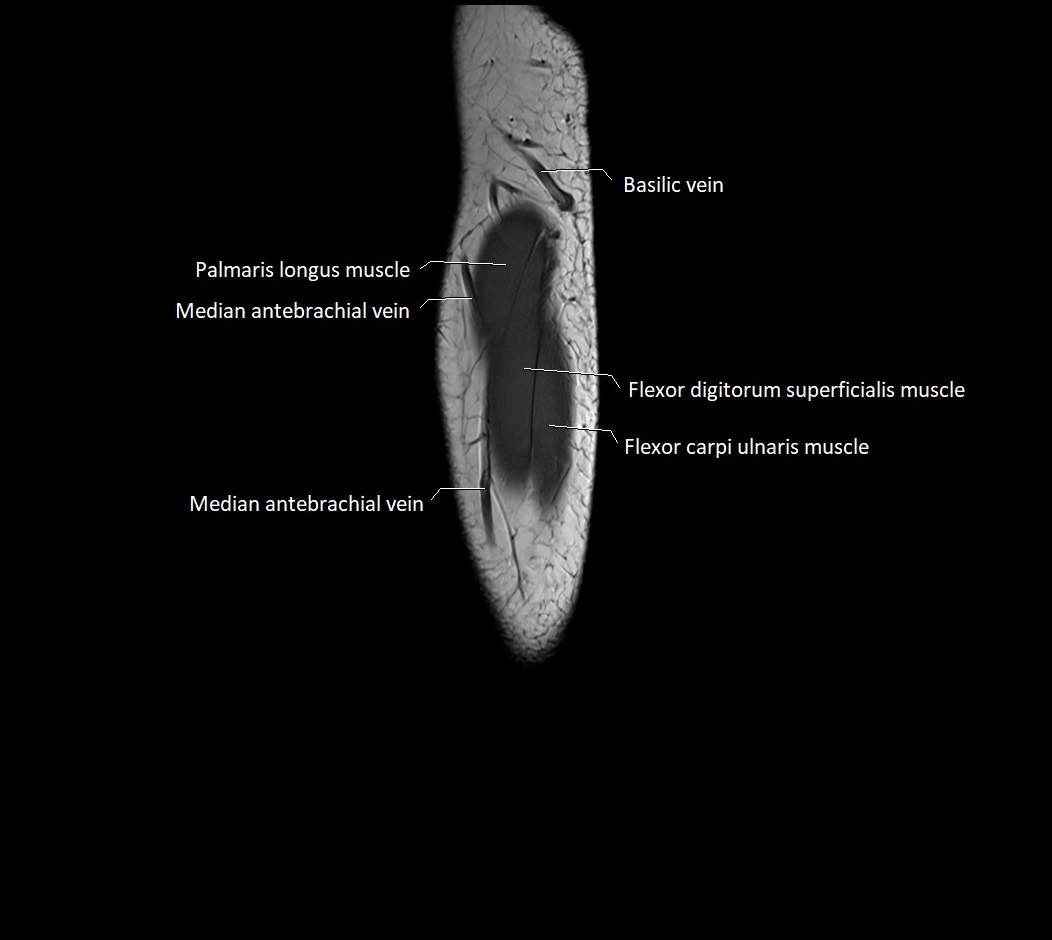

image

MRI images